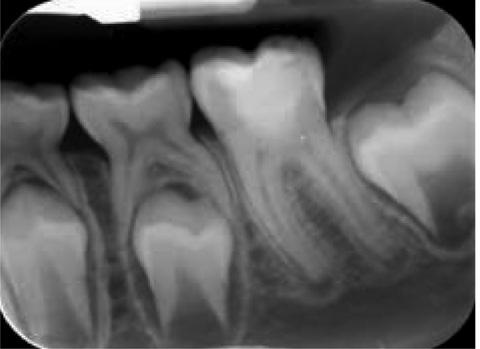

106 Tooth surface protectionfrom concept to clinic

112 The 3D printed permanent crown - Are we there yet?

|

Online Resources for the Dental Profession...